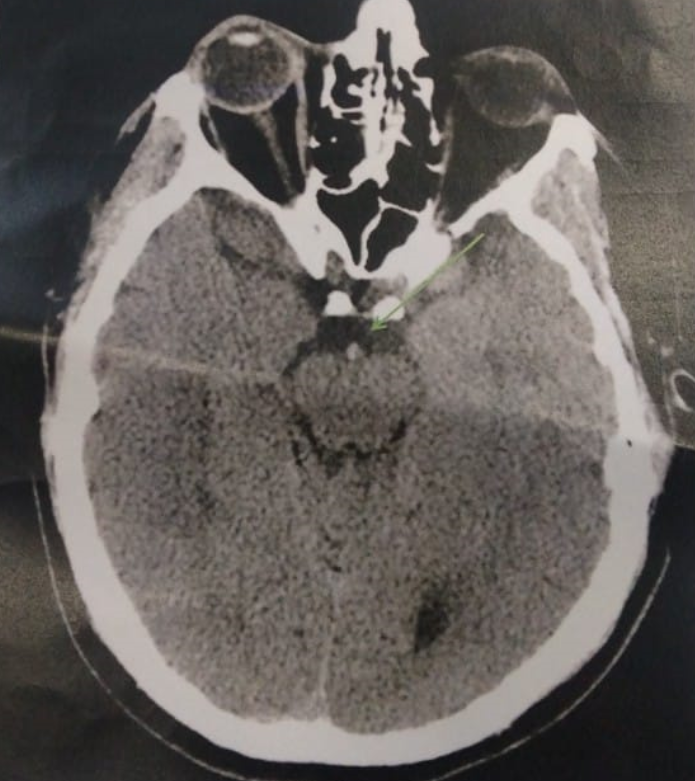

image

Ce patient est un traumatisé crânien. Quels sont les déterminants de l'apport en oxygène au cerveau ? Donner la formule du contenu artériel en oxygène ? Comment réduire la consommation en oxygène du cerveau.. img